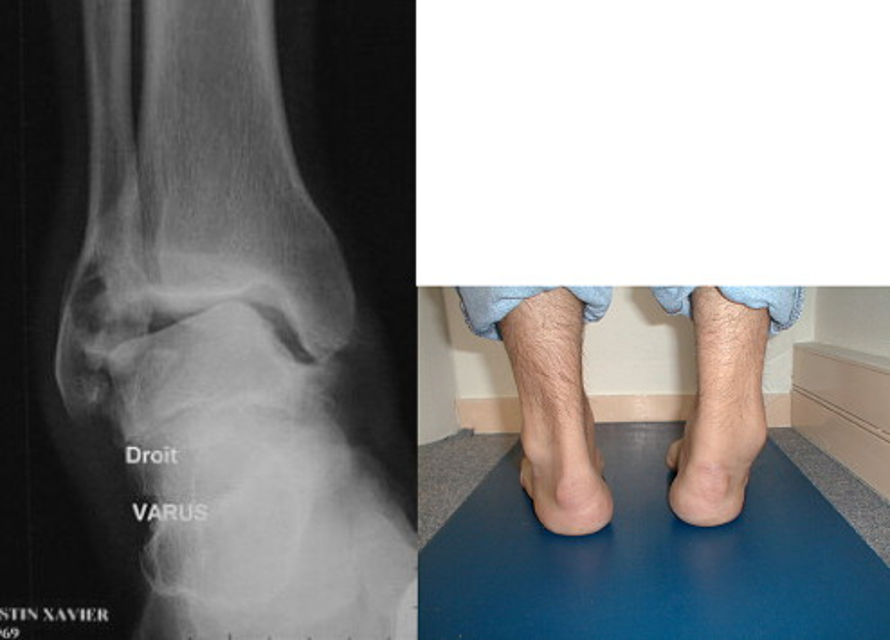

Fonksiyonel Postüral Instabilite: Hindfoot varusu, bağ rekonstrüksiyonu başarısızlıklarına yol açabilir. Bu durum, ayak kenarına aşırı baskı yapar ve postural dengesizliklere neden olur. Varus-equinus gibi morfostatik problemler, instabiliteye yol açabilir.

Arka ayakta varus: Arka ayaktaki kırık düzeltilmediği için fibularis brevis kası rekonstrüksiyonunun başarısızlığı.